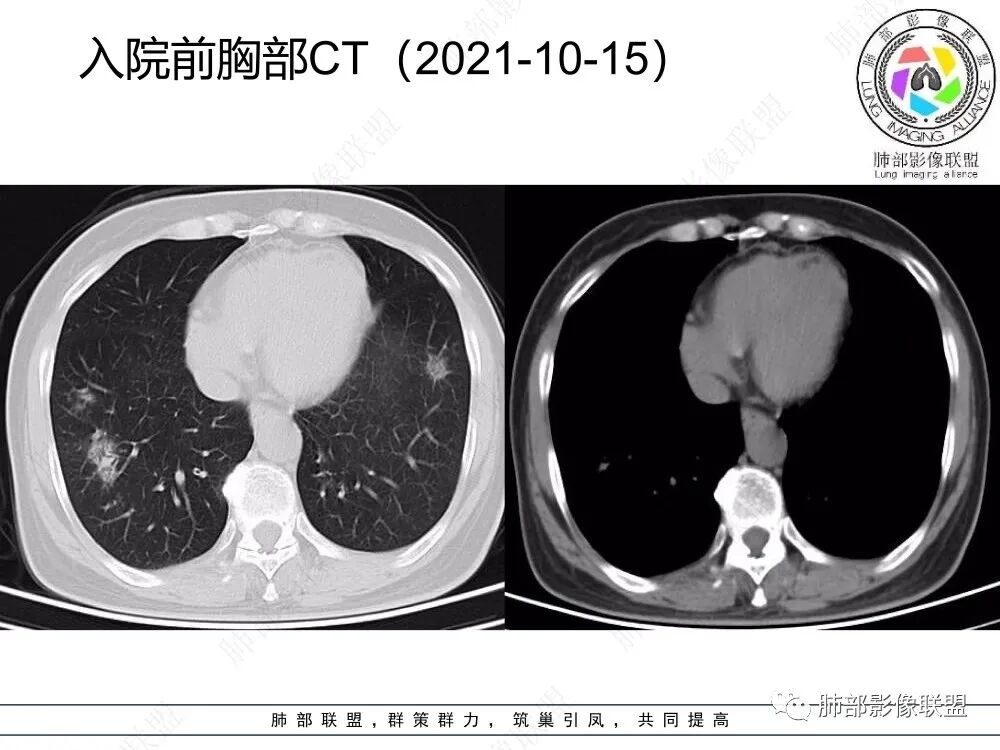

2、CT表现为两肺下叶结节影、斑片影、磨玻璃影,沿支气管血管束分布,部分支气管壁显示增厚。粗略一看部分病灶内似可见“细网格影”,但是仔细观察,可发现此“细网格影”不同于我们常见的“细网格影”,尤其是右肺下叶病灶,可以观察到病灶内部的网格上有高密度结节感或颗粒感,部分层面见“反晕征”,且反晕的边缘亦可观察到结节感。未见胸腔积液。

4、本例急性病程,发热、咳嗽,结合影像多发磨玻璃影表现首先会考虑到感染性病变:①病毒性肺炎,病灶间质分布为主,常较弥漫,外围多见,临床症状重且常与影像表现同步;②支原体肺炎,病变多为1-2叶段、少数多叶段分布,支气管壁弥漫较均匀增厚,可见树芽征、腺泡结节及树雾征;③肺结核,上叶尖后段及下叶背段多见,多灶性、多态性,树芽征,可有空洞、钙化等;④机化性肺炎,病变胸膜下和支气管血管束分布,可有实变、结节及反晕征。

本例病变以两肺下叶为主,非结核好发部位,通常会想到感染性病变,右肺下叶病灶高密度结节感、反晕征,较为符合继发性肺结核(间质浸润为主),但双肺散落的相对柔和淡薄小片影给诊断带来困惑。